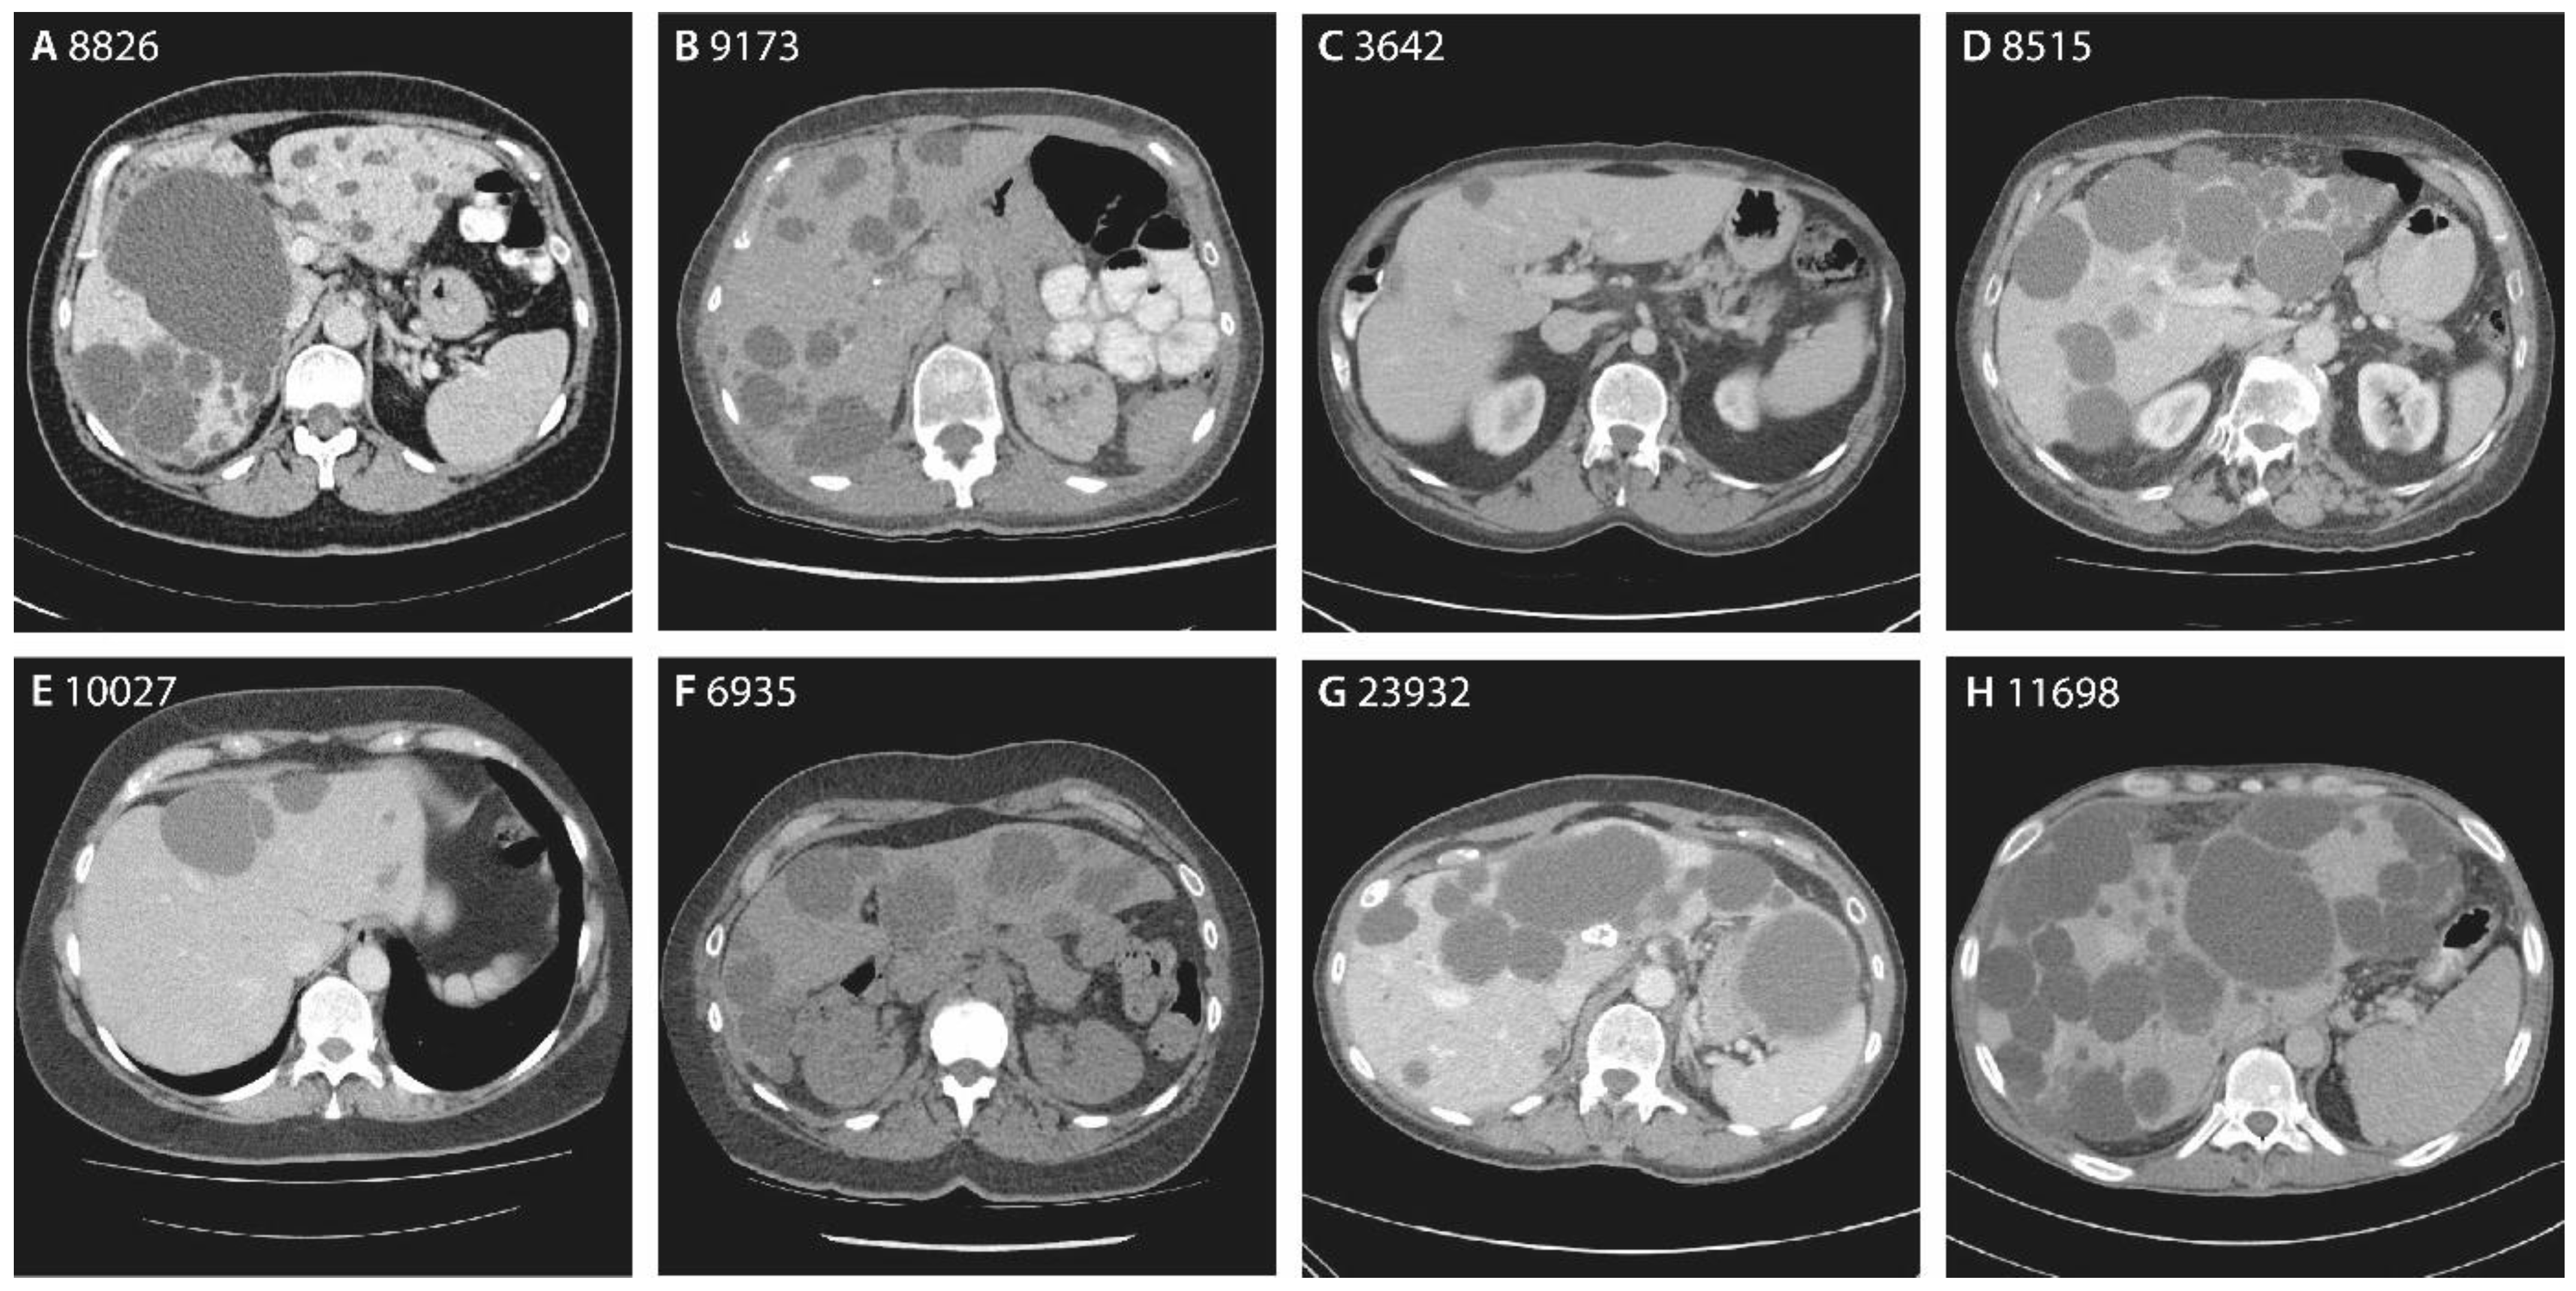

| Chromosome Position | Nucleotide Change | Amino Acid Change | Variant Type | ACMG/AMP | Patient | Sex | Age | Hepatic Cysts | Imaging | GGT | Renal Cysts | eGFR | |

|---|---|---|---|---|---|---|---|---|---|---|---|---|---|

| g.78127372G>A | c.160C>T | p.(Gln54*) | Nonsense | Pathogenic | 9960 | Female | 87 | PLD | US | - | - | - | Family 1 |

| 8826 | Female | 60 | 20+ | CT | 44 | 1 | 69 | ||||||

| 9173 | Female | 44 | 20+ | CT | 15 | 1 | 84 | ||||||

| 9244 | Female | 58 | PLD | US | - | - | - | ||||||

| g.78124118del | c.272delA | p.(Asn91Metfs*5) | Frameshift | VUS | 3642 | Male | 29 | 10+ | CT | 17 | 4 | 89 | |

| 7906 | Female | 50 | PLD | US | - | - | - | ||||||

| g.78121172del | c.371delG | p.(Cys124Serfs*33) | Frameshift | Likely pathogenic | 8515 | Male | 75 | 20+ | CT | 762 a | 1 | >90 | |

| g.78121083C>T | c.460G>A | p.(Gly154Arg) | Missense | VUS | 11549 | Female | 73 | PLD | US | - | - | - | |

| g.78121062T>C | c.478+3A>G | p.? | Splice-site | VUS | 10027 | Female | 56 | 10+ | CT | 29 | 1 | 77 | |

| g.78113978G>A | c.685C>T | p.(Arg229*) | Nonsense | Pathogenic | 6935 | Female | 48 | 20+ | CT | 16 | 0 | 84 | Family 2 |

| 24392 | Male | 68 | PLD | US | - | 0 | 86 | ||||||

| g.78109499dup | c.981dupA | p.(Val328Serfs*28) | Frameshift | Pathogenic | 762 | Male | 66 | 5 | CT | 25 | 3 | 79 | |

| g.78106895G>A | c.1090C>T [36,38] | p.(Arg364*) | Nonsense | Pathogenic | 23932 | Female | 59 | 20+ | CT | 410 a | 0 | >90 | |

| 11409 | Female | 86 | PLD | US | - | - | - | ||||||

| g.78101044del | c.1501delG | p.(Val501*) | Nonsense | Likely pathogenic | 11698 | Male | 57 | 20+ | CT | - | 5 | - | |

| 8094 | Female | 48 | PLD | US | - | 7 | - |